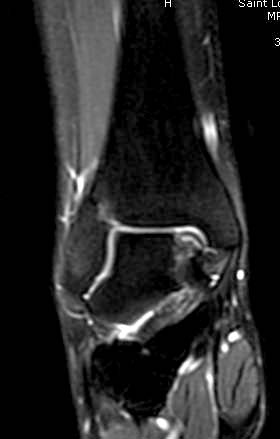

Разбираемый случай не имеет ничего общего с классическим Аваскулярным Некрозом Таранной кости. Здесь так назывемый (osteochondral defect) или osteochondritis dissecans (OCD) таранной кости, при котором патология локализуется в медиально-верхнем нагрузочном отделе. В основном OCD

Симптоматология  OCD выражается слабым отеком, а более сильные боли наступают после физической нагрузки. В отличие от АВН тарана, когда боли постоянные, а при OCD боли изчезают после отдыха. В начальных стадиях

на рентгенограммах не всегда заметны склерозные участки, и поэтому в большинстве диагноз устанавливается поздно. Приход КТ и МРТ улучшил диагностику, и в срезах внутри кисты можно увидеть жидкость, но это не означает проявление симптоматологии. Симптомы проявляются с момента образования внутрисуставных краевых фрагментаций!

При умеренных проявлениях можно ограничиться консервативным лечением, но при выраженной симптоматике необходимо удалить свободные фрагменты.

Артроскопия с дебридментом приносит облегчение, но огромные медиально-верхние дефекты надо замещать. Хирургический доступ через медиальную лодыжку, а для замещения применяют современные алломатериалы.

Для ресторации хряща используем хорошо зарекомендовавший продукт компании DeNovo, который полностью восстанавливает повреждение.